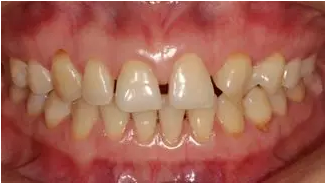

術(shù)前上前牙右側(cè)面照

a7.png

術(shù)前上前牙左側(cè)面照